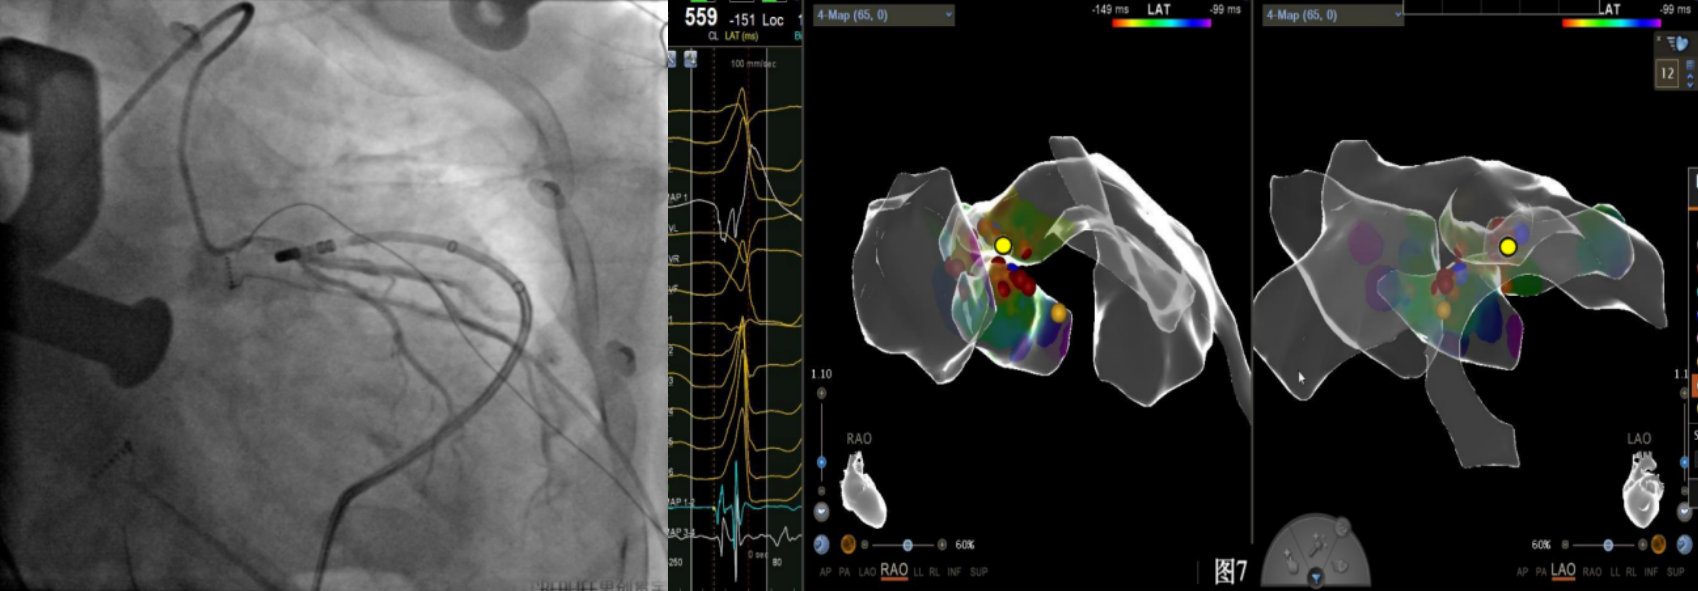

即穿刺股静脉,将消融大头送至冠状窦内,在GCV远端对应位置标测到最早点(图5绿色点)领先体表27ms,消融后早搏未能消失,周明礼评估起源点偏心外膜,能量依旧不能穿透损伤到起源点,内膜消融基本无效后,果断选择难度系数最为复杂的干性心包穿刺心外膜消融。在导丝的指引下,将消融大头送至心包层(图6),于外膜标测到靶点(图7黄色点)电位领先体表31ms,单极电位无r波且有顿挫,ssummit外膜离冠状动脉较近,比较危险,保证安全,进行了冠脉造影(图7),显示距离LAD和LCx有一定距离,相对安全,随即放电,2s室早消失,10s患者出现心率变慢,该区域走形迷走神经节,消融导致心率减慢,随后保证心率正常的情况下,消融够60s,随后观察半小时,早搏没有恢复,手术成功(图8)。经过不懈的努力,患者恢复了窦率,心脏功能也逐渐恢复正常,手术取得了圆满成功。